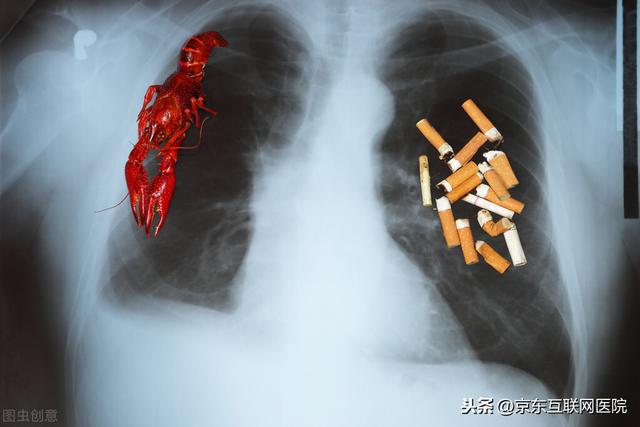

肺がんは喫煙と最も密接な関係がある

中国はタバコ大国で、喫煙者が多い。喫煙者の中には、朝起きてからタバコを吸うのが好きな人もいて、その中毒性はとても強く、歯を磨くのを待てずに急いでまずタバコに火をつける。最新の調査では、この「目覚めの一服」が肺がんや口腔がんのリスクを著しく高めることが判明した。タバコを吸いたくても、起床後30分までは待ったほうがよい。

喫煙者であろうと受動喫煙者であろうと、副流煙であろうと三次喫煙であろうと、その害は初流煙の害にまったく劣らない。

喫煙による肺がんは一般に原発性肺がんを指し、非常に多く、喫煙は肺がんの主な原因であり、肺がんの89%以上は能動喫煙または受動喫煙が原因で、一般に喫煙期間が長いほど喫煙量は多く、特に子供の頃から喫煙している人は多い。

タバコはA級発がん物質であり、毎日副流煙を吸う受動喫煙もニコチン、ベンゾ(a)ピレン、ニトロソアミン、微量ヒ素などの有害物質をタバコの煙にたくさん吸い込むことができ、受動喫煙者は能動喫煙者よりもタバコの煙の有害物質への反応が強い。

肺がんは中国において罹患率、死亡率ともに高い悪性腫瘍であり、喫煙と肺がんには大きな関係がある。データによると、肺がん患者の80%以上は高齢の喫煙者であり、肺がんの80%は喫煙が原因である。

その主な原因は、タバコは燃焼の過程で7000種類以上の化学物質を生成し、その中には60種類以上の発ガン性物質を含む数百種類の有害物質があり、その中でもニコチンは一級発ガン性物質である。データによると、喫煙の量と時間は肺がんの発生に正比例する。つまり、喫煙者の年齢が若ければ若いほど、喫煙時間が長ければ長いほど、喫煙量が多ければ多いほど、肺がんの発生率は高くなり、喫煙者の肺がん発生率は非喫煙者の数十倍、数百倍にもなる。

タバコを長期間吸い続けると、タバコに含まれる有害物質が気管支上皮細胞や扁平上皮などの組織を増殖させ、そこから扁平上皮癌や未分化小細胞癌が容易に誘発される。